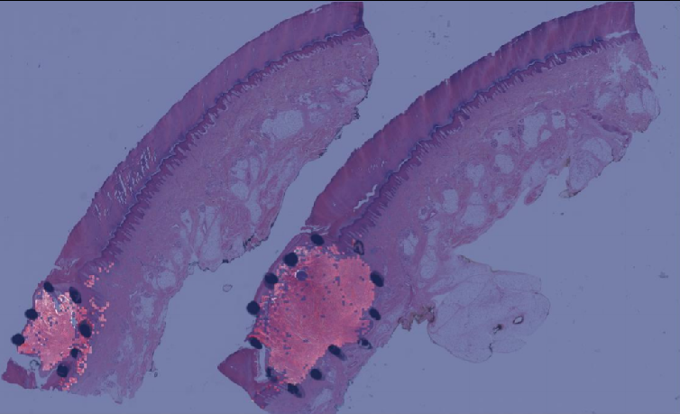

2.3 Model training and assessment

Training patch classifier. A three-class patch classification model (PCLA-3C) was trained on the labeled patches with VGG16 [31] as base architecture (Fig. 2d). Models were trained using this CNN architecture and by backpropagation, we manually changed the last layer’s parameters to optimize the model. The patch classifier would return a WSI with three key scores, corresponding to three categories (melanoma, nevus and other). Slide classification and ROI detection. In the testing stage, all patches from a WSI were first fed into the trained patch classifier. Ignoring patches predicted as other, slide-level prediction was done by majority vote based on patches predicted as melanoma and nevus. If the number of patches labeled as melanoma exceeded the number of patches labeled as nevus in one WSI, we classified it as melanoma, and vice versa (Fig. 2e). For a WSI classified as melanoma, all the patches from this slide will be ranked by melanoma predicted scores. Otherwise, all the patches will be ranked by nevus predicted scores (Fig. 2f). Model assessment. To evaluate the performance of ROI detection, the annotated ratio was measured to calculate Intersection over Union (IoU) for each slide. Given a slide, annotated ratio was calculated by the number of patches in the annotated region divided by the number of patches extracted from the slide: ,where is the number of patches in A (annotated region) and is the number of patches in C (WSI). Then, the top patches based on predicted scores were classified as ROI, where was the total number of patches from a slide. For example, if for a slide in the testing set, it means that 20% of the regions in the slide are ROIs. Then, the model will predict the top 20% of patches (based on the predicted scores) as patches in the ROIs. The performance was measured by Intersection over Union (IoU), which compared the annotated region and predicted ROI region. Since the framework was patch-based, IoU was calculated by the number of patches in the intersection region (the region in both annotated and predicted regions) divided by the number of patches in the union of the annotated and predicted ROI regions: , where shows the number of patches in the region of and shows the number of patches in the region of . A is annotated region and B is the predicted/highlighted region. Visualization. The detection methods could provide three types of visualization maps: boundary, overlap and heatmap (examples were in Fig. 3). Three visualization maps will be generated based on the predicted scores calculated in the ROI detection section (Fig. 2g). The overlap map highlighted top-ranked patches in a WSI and masks other areas with a transparent blue color (Fig. 3a, 3d). The percentage of highlighted patches equaled (the annotated ratio). Therefore, the highlighted region was also the predicted ROI. The boundary map showed the boundary of the largest ROI cluster based on the highlighted patches, where the highlighted patches were clustered by OPTICS algorithm [1] (Fig. 3b, 3e). The last one was a heatmap where red covered regions that had high predicted scores and blue covered regions that had low predicted scores (Fig. 3c, 3f).

(a) Boundary

(b) Overlay

(c) Heatmap

(d) Boundary

(e) Overlay

(f) Heatmap